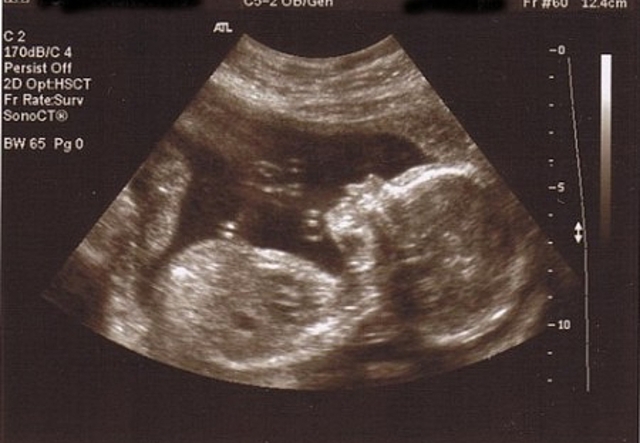

Douglas Howry ,Dorothy Howry,Roderick Bliss and Gerald Posakong published two-dimensional images of the forearm live